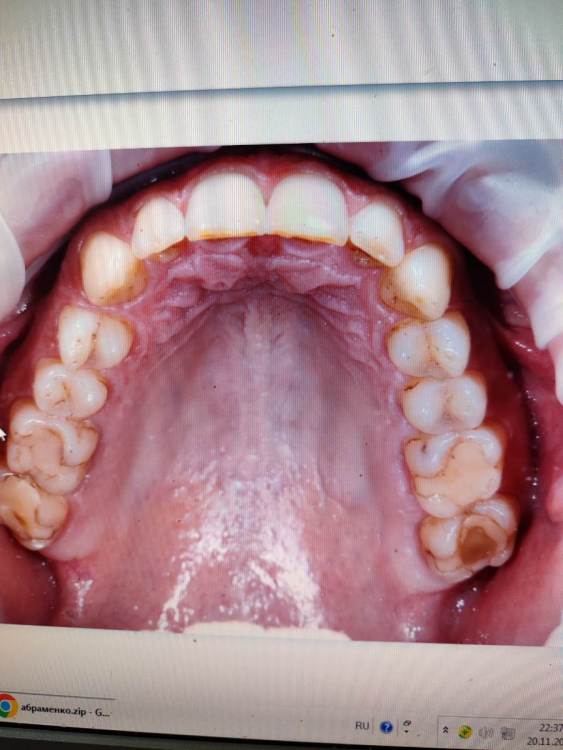

Алексей34679734 Опубликовано 22 ноября, 2023 Автор Поделиться Опубликовано 22 ноября, 2023 @АнтонТЛТ @АнтонТЛТвозможно ли вставить вкладки Ссылка на комментарий

АнтонТЛТ Опубликовано 22 ноября, 2023 Поделиться Опубликовано 22 ноября, 2023 Выглядит так, что можно. Вопрос в количестве здоровых тканей зубов под пломбами. 1 Ссылка на комментарий